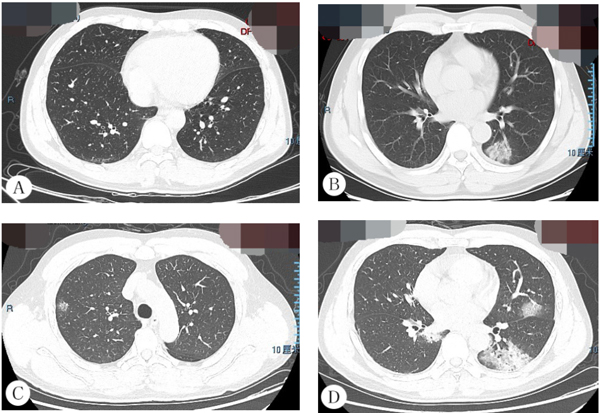

病例1,男,42岁,3天前受凉后开始出现发热,体温最高39.3℃。早期胸部CT未见异常(图1A);5天后出现局限性病变,病变边缘模糊,伴空气支气管征(图1B);5天后继续复查,出现左下肺实变、双肺多发斑片状磨玻璃影(图1C-D)。

图1 病例1胸部CT影像表现